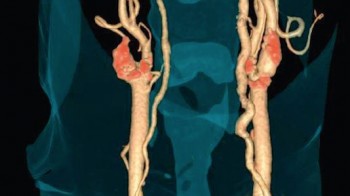

CT-kolonografija

Karcinom kolona (debelog crijeva) je drugi po  učestalosti međju karcinomima kod muškaraca (iza karcinoma pluća) te treći po učestalosti kod žena (iza karcinoma dojke i cerviksa) i najsigurniji nacin rane detekcije jeste uraditi kolonoskopiju. Osim klasične endoskopske metode, danas imamo na raspolaganju i mogućnost CT kolonoskopije, koja je puno jednostavnija i za pacijenta komfornija, a po rezultatima nalaza komparabilna s klasičnom kolonoskopijom.  U 22 američke savezne države kolonoskopija je pregled koji ide na teret fonda zdravstvenog osiguranja.

Šta je CT kolonografija?

CT kolonografija ili virtualna kolonoskopija je procedura koja koristi viseslojni CT za pregled debelog crijeva na prisustvo karcinoma ili prekanceroznih polipa. Njome se mogu otkriti tumori, polipi, krvarenje, upalne bolesti crijeva te divertikuloza.